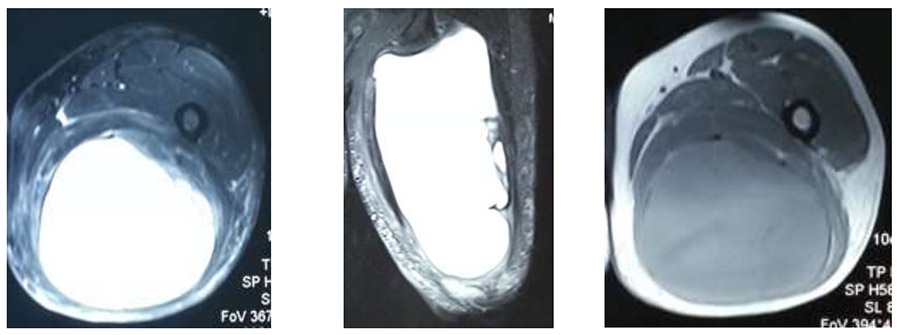

Ameliyat Öncesi: MR’da büyük kist alanının eşlik ettiği düzensiz sınırlı kitle görülmekte